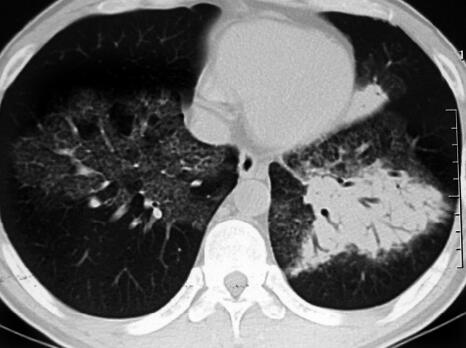

治疗1周后,患者体温恢复正常,气短较前好转,肺部干鸣音消失,仍可闻及散在湿啰音,胸部CT示胸腔积液吸收,斑片影无明显变化(图3)。治疗1个月后,患者无临床症状,复查血常规正常;复查胸部CT示双肺斑片影较前明显吸收(图4)。

图3